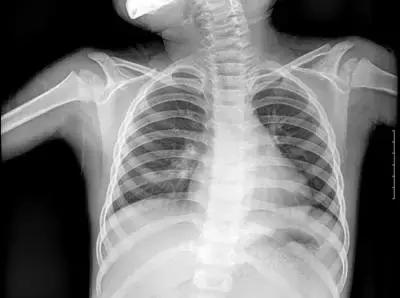

但人体各策划结构的密度不同,X线穿透时被吸收的量不同,就形成了黑白灰分明、层次显著的“片子”。看图举例子:

▲X射线成像图

骨骼、钙化灶、体内液体等(听起来质地较厚重的策划),吸收X光较多,因此形成白色影像,也就是传说中的“高密度影”,上图的上臂、肋骨就是如此。

呼吸道、胃肠道、脂肪策划(听起来质地较疏松),吸收X光较少,在片子上呈现黑色影像,即“低密度影”,图中含气体较多的肺脏是代表。

再就是密度居中的实质器官、 肌肉、结缔策划,比如心脏,在片子上呈现的影像介于黑白两色之间。

X光片“泾渭分明”的特点帮医生辨别身体的不同病变。

骨折、肋骨病变,密度高的骨骼白色影像哪里出问题一目了然,比如液气胸等肺部及气道病变,肺脏的黑色影像中就会混入明亮的白色。